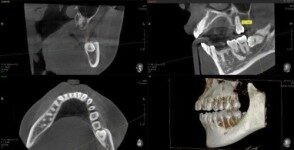

歯科用CTを使用します

親知らずは、生え方や位置によってお口の健康に影響を及ぼすことがある歯です。まっすぐ正常に生えている場合は問題が起こらないこともありますが、斜めや横向きに生えている場合には歯ぐきの炎症やむし歯の原因になることがあります。特に親知らずと奥歯の間は汚れがたまりやすく、気付かないうちにむし歯や智歯周囲炎と呼ばれる炎症を引き起こすこともあるため、早めに状態を確認することが大切です。

また、親知らずは複雑な生え方をしていることも多く、歯ぐきを切開したり骨を調整したりして抜歯を行う場合があります。伊藤歯科医院では、歯科用CTを用いて三次元的に画像を確認し、親知らずの位置や下歯槽神経との距離を把握したうえで診療を行っています。安全性に配慮した診査を行いながら、患者様が安心して治療を受けられるよう丁寧な説明と処置を心がけています。